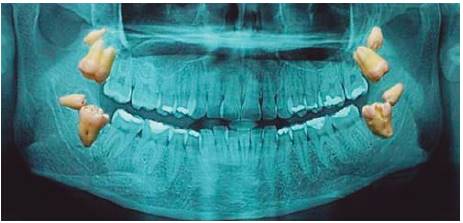

Fourth molars are formed and develop like any other teeth although in some instances it might not possess the same evolutionary moment as teeth in the area, they can erupt into the arch in a position very similar to that of a molar, or they can remain within the bone.16 They can be found in upper and lower jaws (Figures 7y8), they can be unilateral or bilateral, or they can even be found in both jaws.

When fourth molars appear bilaterally in both jaws (Figure 9) they can (or cannot) be associated to syndromes such as: cleidocranial dysplasia, Down’s syndrome, Leopard’ s syndrome, Gardner’ s syndrome, Ellis Van Creveld syndrome, facial orodigo disostosis, Crouson’ s syndrome, Hallerman Streiff syndrome, Sturge-Weber syndrome and cleft lip or palate among others. All the aforementioned syndromes exhibit in common the presence of facial cranial anomalies. Table I describes other examples.12,18,19,20

Combination of environmental and genetic factors, although hereditary transmission of fourth molars has not been yet proved.12,23,31 They most frequently appear in patients with familial history of such teeth.21 Presence of multiple supernumerary teeth have been reported in one single family, occurring as a non-syndromic trait. Non syndromic dominant autosomal transmission of multiple supernumerary teeth is new.20 Thus, a dominant autosomal heritage with incomplete penetration has been proposed as genetic theory, or being linked to chromosome X, this would explain recurrence in the same family and in monozygotic twins, such as was the case of two siblings with bilateral distomolars (Figures 18 y 19) presented by Dr Daniel Cortes Caballero.12,21,23,31